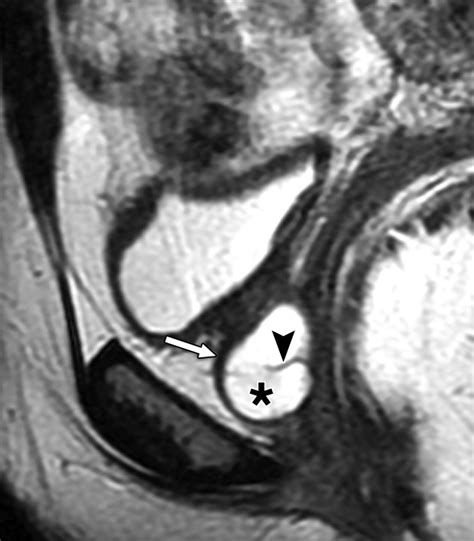

MRI (Magnetic Resonance Imaging) The gold standard for visualizing the size and location of the diverticulum.

Voiding Cystourethrogram (VCUG) Uses contrast dye to see if the pouch fills during urination.

Urethroscopy Direct visualization of the urethra using a thin camera to locate the diverticular opening.